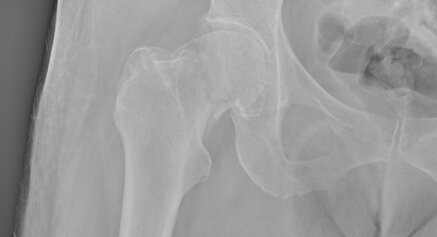

La diagnosi è prevalentemente clinica, raccolta una esaustiva anamnesi e dopo un completo esame obiettivo. Per valutare il danno articolare e quindi poter stadiare l’artrosi, vengono eseguite dal paziente delle radiografie del bacino per anche e dell’anca interessata in due proiezioni. Radiograficamente l’artrosi si caratterizza da: restringimento della rima articolare, osteosclerosi, presenza di osteofiti e geodi.